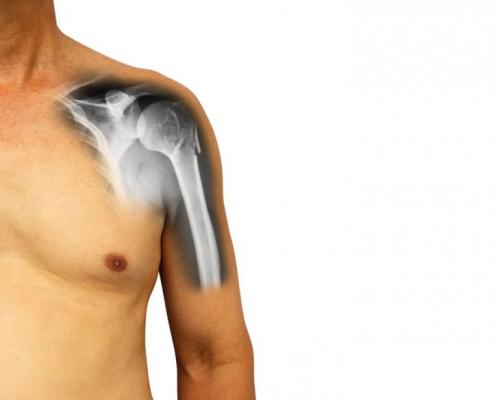

Перелом плеча сколько длится лечение. Причины и виды травмы

У пожилых людей травма плеча встречается чаще, нежели у молодых, что связано с физиологическими, возрастными изменениями в организме, в силу снижения содержания кальция и других микроэлементов, отвечающих за минерализацию костей. Подвержены травме и дети, у которых кости еще не окрепли и не развились навыки правильного группирования при падении.Еще одна причина перелома плечевой кости – вывих в области плечевого сустава с сопутствующим резким сокращением мышечных волокон. Встречается данная патологическая картина по причине чрезмерной нагрузки у спортсменов в процессе активных физических занятий.

Перелом в районе плечевой кости классифицируют на виды, в соответствии с местом локализации и сопутствующими осложнениями:

Наиболее тяжелыми видами травмирования считаются открытый, со смещением и оскольчатый перелом плечевой кости. При открытом переломе поврежденная часть кости с острым концом разрывает мягкие ткани и кожу, образуется рана с кровотечением.

При переломе плеча со смещением костей острые края обломков могут повредить кровеносные сосуды и корешки нервных окончаний. В первом случае существует риск открытия кровотечения, в другом – нарушение функции нервного окончания способно спровоцировать нарушения чувствительности конечности и в дальнейшем привести к полной обездвиженности.

Оскольчатый перелом – сложный в плане лечения. Перед тем, как фиксировать плечевой пояс гипсом, проводится операция по восстановлению первоначального положения костных обломков. Если части кости слишком мелкие или же тотально поврежденные, потребуется проведение протезирования.